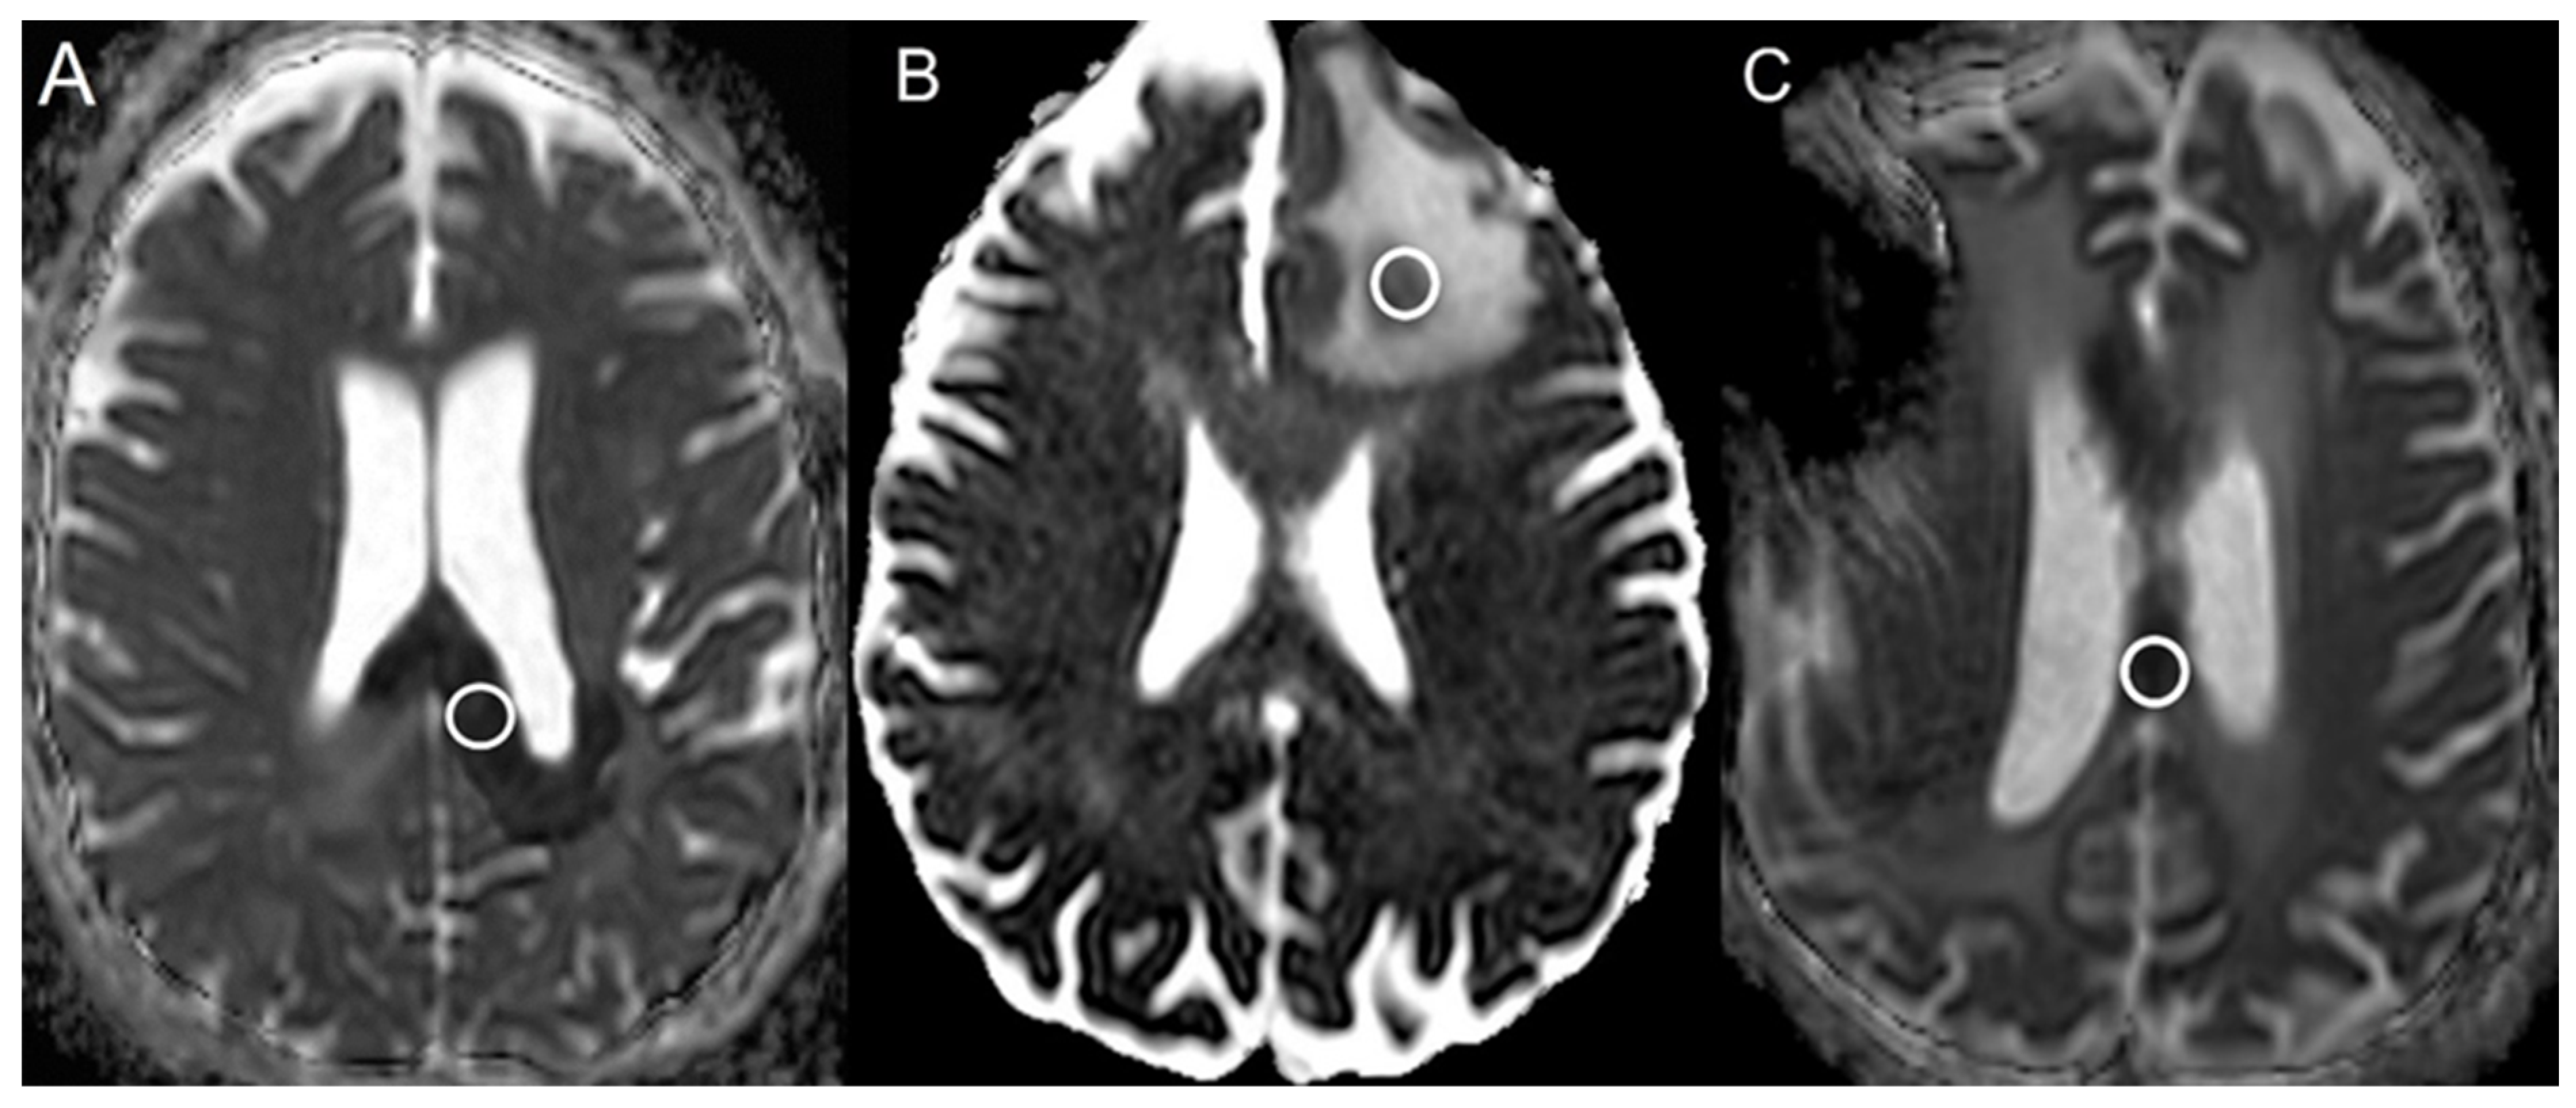

| Bevacizumab | 21 | 248.1 ± 67.2 | 647.2 ± 94.6 | <0.001 |

| Progressive glioblastoma | 49 | 752.8 ± 132.5 | 709.2 ± 63.5 | 0.08 |

| Radiation necrosis | 58 | 479.0 ± 105.2 | 723.3 ± 64.0 | <0.001 |

| Bevacizumab | 1.00 | N/A |

| Progressive glioblastoma | 0.59 | 0.41–0.70 |

| Radiation necrosis | 0.98 | 0.95–1.00 |

| Bevacizumab | 21 | 0.39 ± 0.10 |

| Progressive glioblastoma | 49 | 1.07 ± 0.22 |

| Radiation necrosis | 58 | 0.66 ± 0.14 |